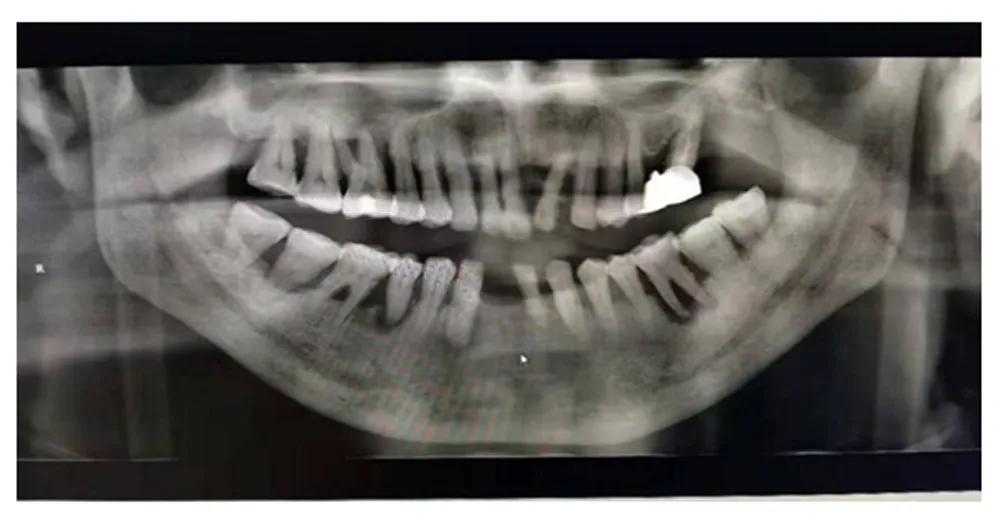

有过看牙经验的人都知道,在一些项目治疗前,牙医会让先拍X光片。牙科常用的X光片主要有三种:小牙片、全景曲断片和牙科CT。今天,我们详细介绍其中一种常用的X光片——全景片。

全景片又称曲面体层片,可以在一张胶片上完整、清晰地显示上颌骨、下颌骨全貌,上下颌牙列情况,牙槽骨情况,能清晰显示上颌窦腔、窦壁、窦底情况,以及颞颌关节情况,并对颌骨周围疾病的诊断提供帮助。

全景片可以为医生术前诊断、分析提供全景样图像依据,以便能更好地为患者设计治疗方案,可有如下作用~~

1.牙齿的解剖结构、密度、牙周状况的检查。

2.埋伏牙和智齿的长势、牙根位置和面部神经的距离。

3.牙齿发育情况的判断。

4.牙齿缺失修复前基牙的判断。

5.根管充填、镶牙、种植、矫正的评估及复查。

6.头面部外伤骨折的诊断。